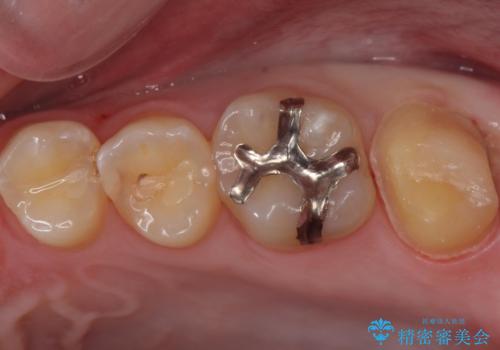

- 奥歯が欠けてしみるとのことで来院された患者様です。

かなり大きな虫歯であることと、清掃不良により歯全体が脱灰していたため、クラウンでの修復処置を行います。

奥に生えている親知らずも清掃不良であったため、今回治療する歯の清掃性を高めるために抜歯を行います。